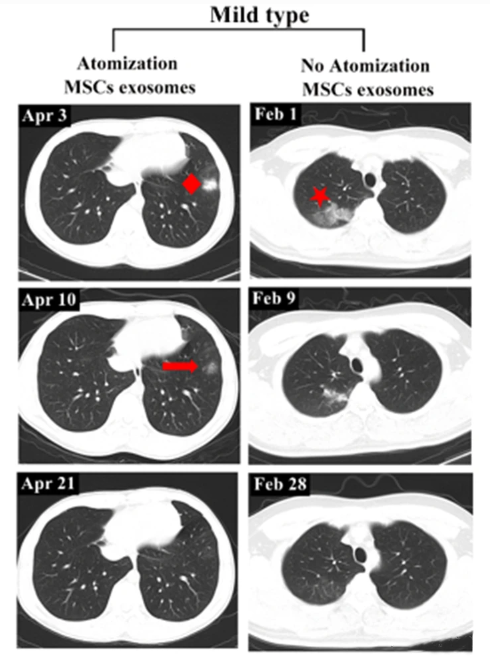

干细胞外泌体是干细胞分泌的一种微小囊泡,直径仅30-150纳米,虽然微小,却携带了大量的生物活性物质,如蛋白质、核酸和脂质。这些物质能够与损伤细胞“交流”,调节细胞功能,起到抗炎、免疫调节和组织修复的作用。特别是间充质干细胞(MSC)来源的外泌体,因其低免疫原性和高安全性,能避免传统药物可能引发的副作用,在治疗呼吸道疾病时展现出巨大潜力。2022年,发表在《Stem Cell Reviews&Reports》的一项临床研究,为干细胞外泌体雾化治疗新冠肺炎的安全性和可行性提供了有力证据。在这项研究中,7名新冠肺炎患者(其中2名为重症,5名为轻症)接受了脐带间充质干细胞外泌体的雾化治疗。结果表明,外泌体治疗不仅安全可靠,还显著加速了肺部病变的吸收,并缩短了轻症患者的住院时间。尤其值得注意的是,在感染早期进行外泌体雾化治疗的效果更加显著。并且是越早使用外泌体雾化治疗,效果越好。研究中的轻症患者在接受外泌体雾化治疗后,仅用18天就实现了肺部病变的完全吸收,而未接受该治疗的患者则需要27天。

▲左:有外泌体雾化治疗的轻症病例。右:无外泌体雾化治疗的轻症病例

这一结果说明,早期干预不仅能加速病情恢复,还可避免肺部损伤的进一步恶化。对于轻症患者而言,快速康复的优势尤为明显。研究中还包括了一例重症患者,该患者自2020年2月27日开始接受外泌体雾化治疗,至3月18日的CT扫描结果显示,其双肺病变明显吸收,病变密度显著降低。到4月1日,患者肺部病灶完全吸收。相比之下,未接受外泌体雾化治疗的另一名重症患者,虽然肺部病灶也有所吸收,但依然残留纤维脐带样阴影,康复情况不及前者理想。